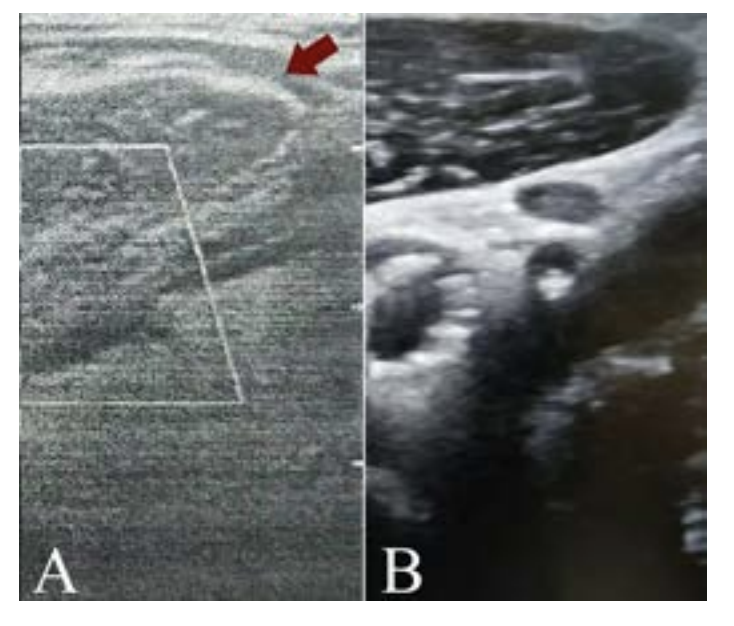

One hour later, the patient started to complain of neck pain at the site of intervention, and we observed a small supraclavicular soft swelling. Ultrasound was performed and revealed a fluid collection around the sternomastoid muscle with no continuation with the CCA or any of its branches (Figure 3A).

After 4 hours the ultrasound confirmed that the size of the hematoma was not increasing and patient symptoms started to resolve. At 24 hours the ultrasound confirmed that the hematoma size was decreasing so the patient was discharged home almost asymptomatic. Finally, the one week follow up ultrasound examination confirmed complete resolution of the hematoma and the patient was completely asymptomatic (Figure 3B).